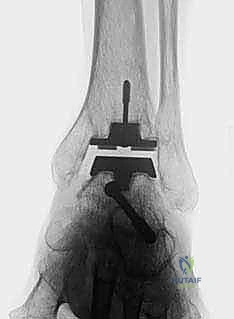

5. زراعة نظام TNK النهائي

بمجرد التأكد من المقاسات والزوايا المثالية، يتم زرع المكونات النهائية. يتم إدخال المكون الظنبوبي المعدني بقوة ليثبت في العظم، يليه المكون الكاحلي. أخيراً، يتم إدخال الح